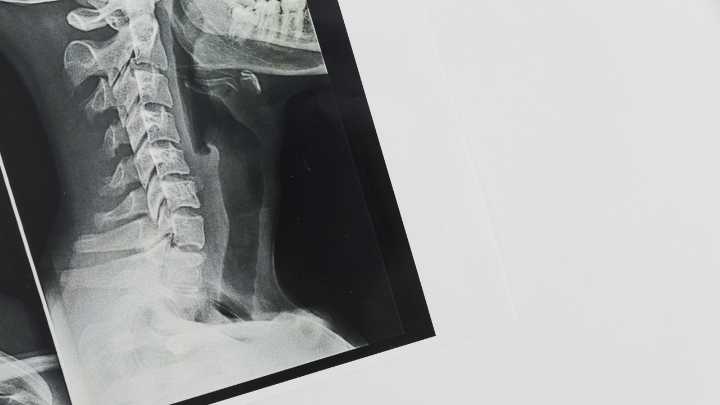

Uno de los grandes misterios del sarcoma de Ewing , un tumor pediátrico de gran agresividad , es saber dónde se origina. Una información vital para poder encontrar formas más efectivas de actuar sobre él.

Ahora esta incógnita parece resuelta, gracias al trabajo de un equipo multicéntrico que han liderado el Instituto de Investigación del Hospital del Mar y el Institut de Recerca Sant Joan de Déu y que publica la revista científica ' Nature Communications '. Este trabajo abre la puerta a averiguar qué factores desencadenan la progresión del tumor y sus posibles vulnerabilidades.